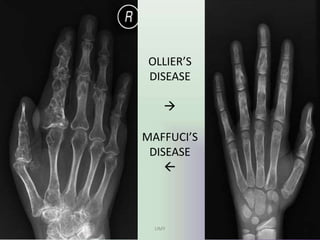

OLLIER”S DISEASE

• Ollier disease also known as

enchondromatosis, is a non-

hereditary, sporadic, skeletal

disorder characterised by

multiple enchondromas that are

principally located in the

metaphyseal regions.

• Plain films show multiple

enchondromas. Larger lesions can

show cartilage calcification in a

typical rings and arcs pattern.

• Imaging characterestics are of

same as ENCHONDROMAS

MAFUCCI’S SYNDROME

UMY

• Maffucci syndrome is a congenital non

hereditary mesodermal dysplasia characterised

by multiple enchondromas with soft-tissue

cavernous haemangiomas.

• Imaging findings are

multiple enchondromas seen associated with

soft tissue swelling and phleboliths.

• Enchondromas degenerate into

chondrosarcomas in 15-51% of cases and soft-

tissue haemangiomas to vascular sarcomas in

3-5%.

OLLIER’S

DISEASE



MAFFUCI’S

